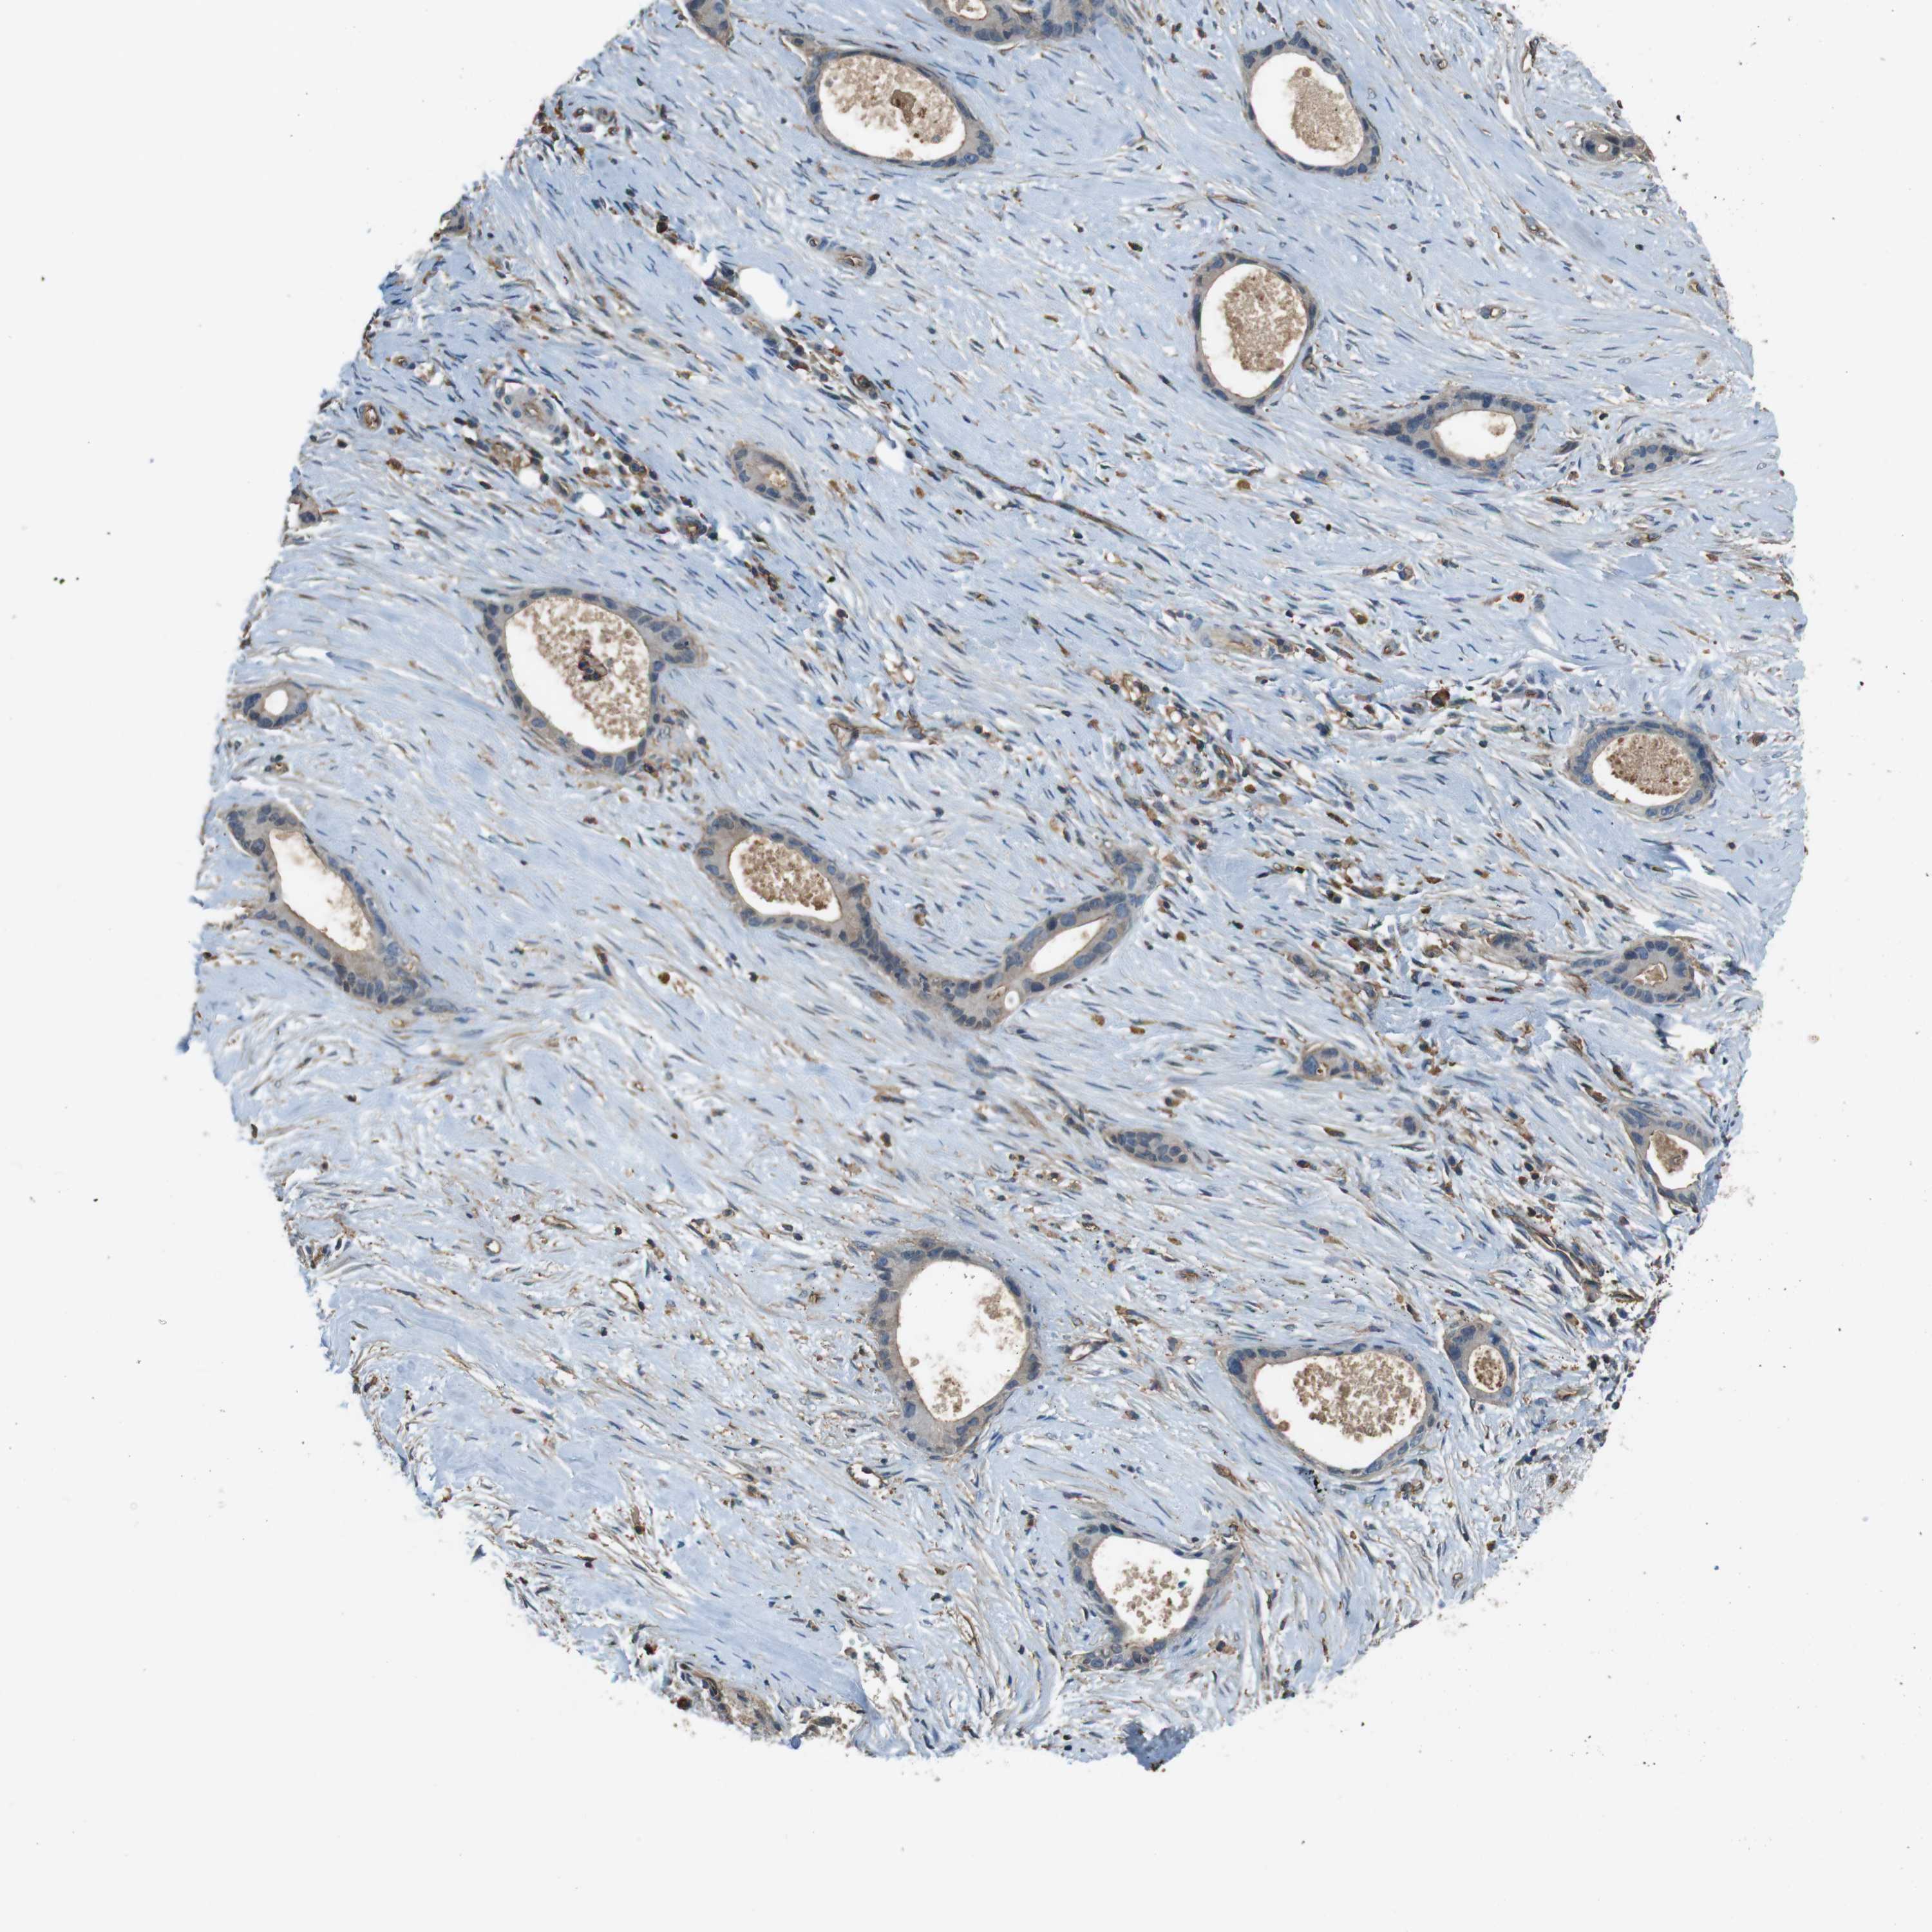

LIVER CANCER - Protein expressioni

A mouse-over function shows sample information and annotation data. Click on an image to view it in a full screen mode. Samples can be filtered based on level of antibody staining by selecting one or several of the following categories: high, medium, low and not detected. The assay and annotation is described here.

Antibody stainingi

Antibody staining in the annotated cell types in the current human tissue is reported as not detected, low, medium, or high, based on conventional immunohistochemistry profiling in selected tissues. This score is based on the combination of the staining intensity and fraction of stained cells.

Each image is clickable and will lead to virtual microscopy that enables deeper exploration of all samples and also displays staining intensity scores, fraction scores and subcellular localization as well as patient and tissue information for each sample.

Antibody HPA014050

Staining

High

Medium

Low

Not detected

Intensity

Strong

Moderate

Weak

Negative

Quantity

>75%

75%-25%

<25%

None

Location

Nuclear

Cytoplasmic/membranous

Cytoplasmic/membranous,nuclear

Cholangiocarcinoma

Carcinoma, Hepatocellular, NOS